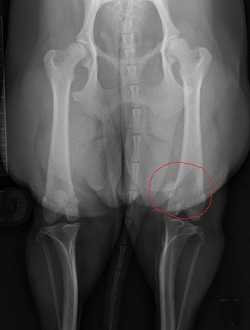

X-ray: X-rays (radiographs) can confirm a displaced patella. The relocation of the patella can be observed in the x-rays as being either towards the center-line of the dog's body (called medial patellar luxation or MPL) or in the opposite direction (called lateral patellar luxation).

In the x-ray image here, the 12-month-old cavalier's right patella, outlined in red, can be seen to be displaced medially (towards the center of the dog's body), when compared with the left patella, which is in its proper location in the center groove of the upper leg bone, the femur.